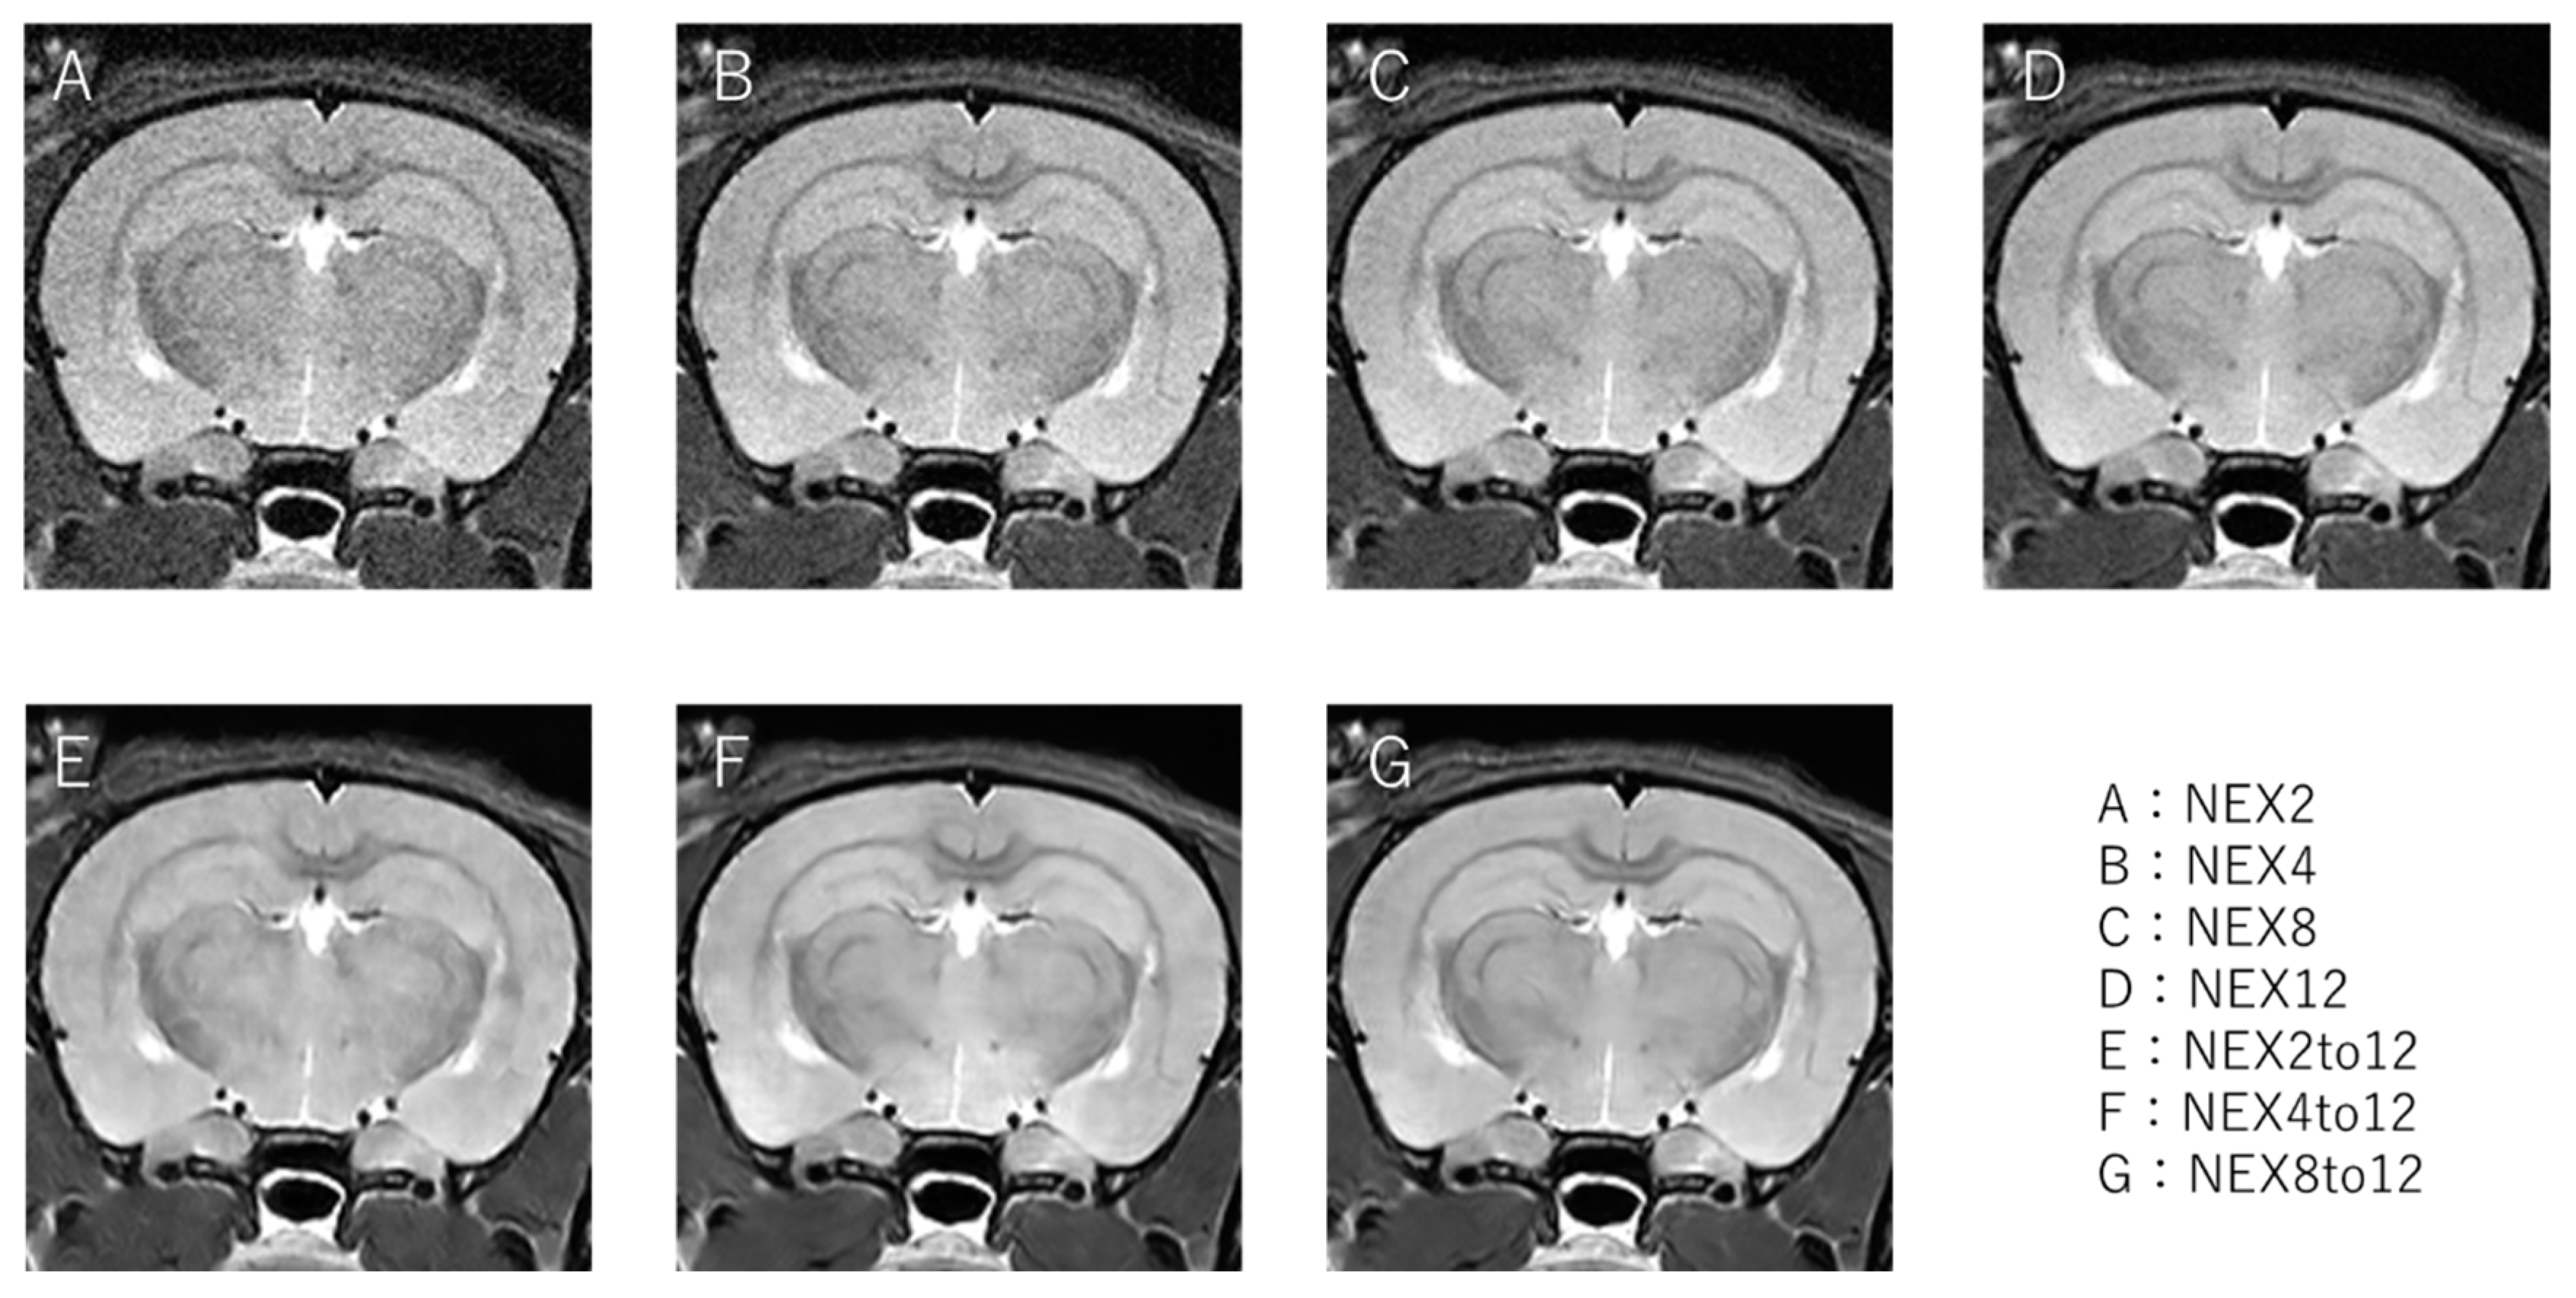

The results of the input image, teacher image, and image reconstructed using the RDN are shown in Figure 2. The input images were the NEX2, 4, and 8 patterns, the teacher image was NEX12, and the reconstructed images were NEX2 to 12, 4 to 12, and 8 to 12.

Input images with low NEX ((A): NEX2, (B): NEX4, (C): NEX8), teacher image ((D): NEX12), and reconstructed images (E–G), where (E) is the image obtained by reconstructing NEX2, (F) is NEX4, and (G) is NEX8 with RDN. NEX, number of excitations.